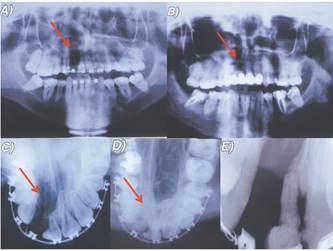

Paciente D.C.R de 16 años de edad, sexo masculino, acude a la Unidad de Malformaciones Craneofaciales de la Facultad de Odontología de la Universidad de Chile para tratamiento de Ortodoncia, con fístula buconasal de 2,1 cm de diámetro en sentido transversal en su diámetro mayor, como secuela de fisura unilateral derecha de labio, paladar y velo. El paciente presenta una clase II esqueletal con falta de desarrollo del tercio medio facial. En sentido sagital presenta una distoclusión molar bilateral y un resalte negativo de -0.5 mm, en sentido transversal una mordida cruzada bilateral y en sentido vertical un escalón disminuido, con un valor de 0 mm.

El paciente fue operado en 4 oportunidades para el cierre del paladar; al año y seis meses, a los 4 años, 9 años y 12 años.

Se realiza interconsulta a Cirugía Plástica para la evaluación del cierre de la fístula y coordinar el inicio del tratamiento de ortodoncia. Este último se planifica en base a la realización de una expansión (mínima) del maxilar para la mejora en sentido transversal de la anomalía, de acuerdo a lo conversado y coordinado con el cirujano, para posteriormente alinear y nivelar las arcadas mediante tratamiento correctivo.

Se decide coordinar una nueva cirugía de paladar para el cierre de la fístula mediante injerto de lengua (cicatrización por 1° intención) y el desligue a las 3 semanas (cicatrización por 2° intención). A los 6 meses de realizada esta cirugía se decidió realizar injerto óseo alveolar derecho para lo cual se prepara ortodóncicamente la posición de dientes adyacentes.